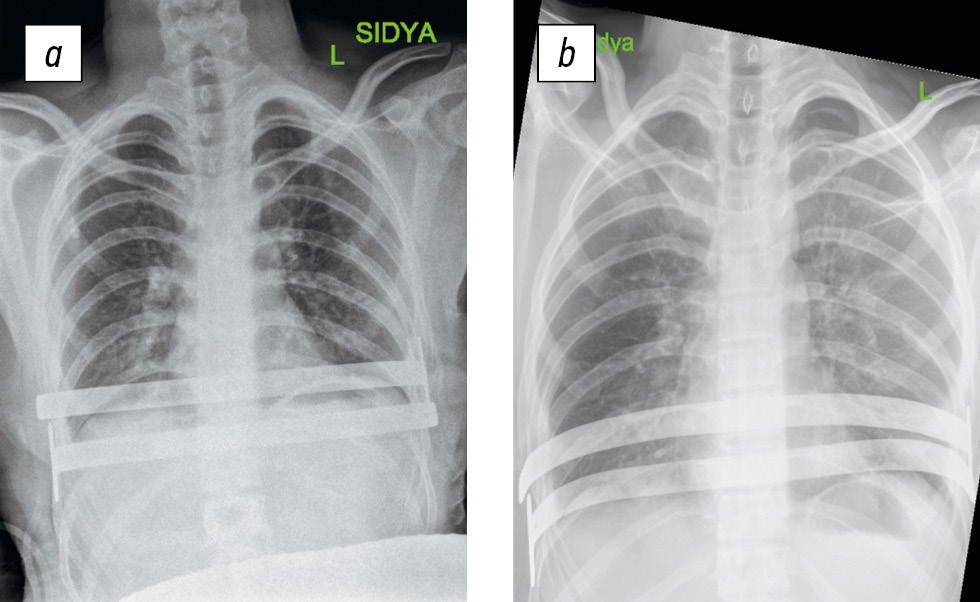

На проведенной компьютерной томографии (КТ) грудной клетки установлен островершинный тип килевидной деформации грудной клетки тяжелой степени (рис. 1).

Рис. 1. Компьютерная томограмма грудной клетки пациента Г., 17 лет до начала оперативного лечения в горизонтальной плоскости (a), в сагиттальной плоскости (b). Индекс Галлера 1,4, угол ротации грудины 12° вправо, индекс компрессии 0,9.